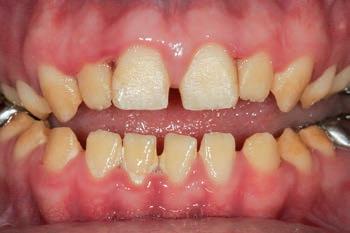

1: The patient’s initial situation on clinical presentation to the tertiary care referral centre. The dentition is globally af fected by amelogenesis imperfecta, associated with dentoalveolar disproportion and an unusual presentation of open occlusion.

The patient was an 18-year-old male with a confirmed family history of Xlinked AI, who was otherwise in good health and non-smoking. Upon initial clinical presentation, a low-caries-risk, complete adult dentition from second molar to second molar was present, which was globally affected by pitted, hypoplastic and hypomineralised AI, dento-alveolar disproportion and an unusual generalised open occlusion, characterised by one occlusal contact at the right first molar region in the maximum intercuspation position (MIP). Historical paediatric management of the dentition involved placement of stainless steel crowns at the first permanent molar sites to protect the emerging dentition from post-eruptive breakdown and loss of occlusovertical dimension during the mixed dentition phase.6 On adult presentation, all but the UR6 stainless steel crown remained intact. Oral hygiene was poor, with evidence of plaque-induced chronic gingivitis (Figure 1). The patient reported experiencing severe, widespread hypersensitivity upon hot, cold, osmotic and masticatory stimuli, and feeling aesthetically self-conscious. The patient was seeking comprehensive fixed prosthodontic care and was well informed about the nature of such treatment, having witnessed his elder siblings undergo similar treatment.

Clinical case